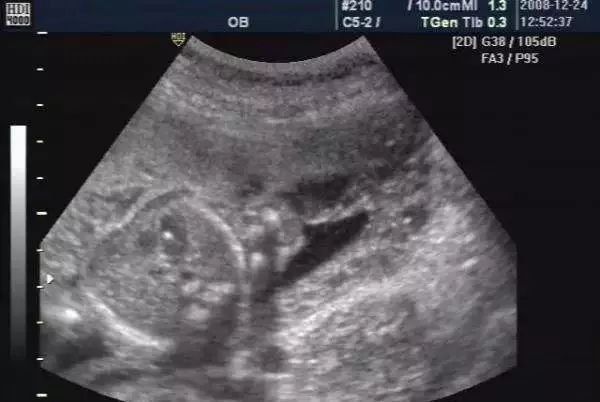

随着医学的进步,B超机的分辨率越来越高。以前孕检中看不到的胎儿情况看的越来越清楚了,有时候没有什么大问题,可人家B超医生看见什么就要报告什么,结果让很多准妈妈非常担心。比如在怀孕期间宝宝做了B超检查,发现胎儿左心室里面有一个强光斑,这可是个不少孕妈都会遇到的揪心问题。

其实胎儿心室内点状强回斑是一个声像图表现,而不是一种心脏畸形,更不是一种心脏异常诊断。

胎儿左心室的强光斑又称强光点或者强回声,其实不仅仅是左心室,右心室也可以发现,胎儿心室内这种强回声光斑,一般是:胎儿心室内腱索增厚形成的强回声反射、乳头中央矿物沉积、乳头肌腱索不完全穿孔等。

孕妇也不要紧张,这种强回声光点并不增加胎儿患染色体异常的这种风险,可以定期观察,还需要结合早期的检查综合评估。比如孕早期NT是否增厚,或者唐筛、无创检查结果是否正常,再结合孕妇的年龄来判断胎儿有没有患染色体异常的风险。

通常情况下,大部分心室强回声点随孕周增加而缩小,回声强度也逐渐减弱,渐渐模糊不清,到足月妊娠几乎完全消失。少数则可一直存在,直至分娩,甚至产后超声仍能观察到。对于大部分胎儿而言,如果没有其它方面异常,心室内强回声点可能并无无重要的临床意义。

胎儿心室强光斑不是心脏病的表现,也存在极少数宝宝染色体异常的风险,那么到底有多大的风险,这个风险的概率目前尚不能确定,大概在1/500左右。大多数的孩子是没有什么大的问题。